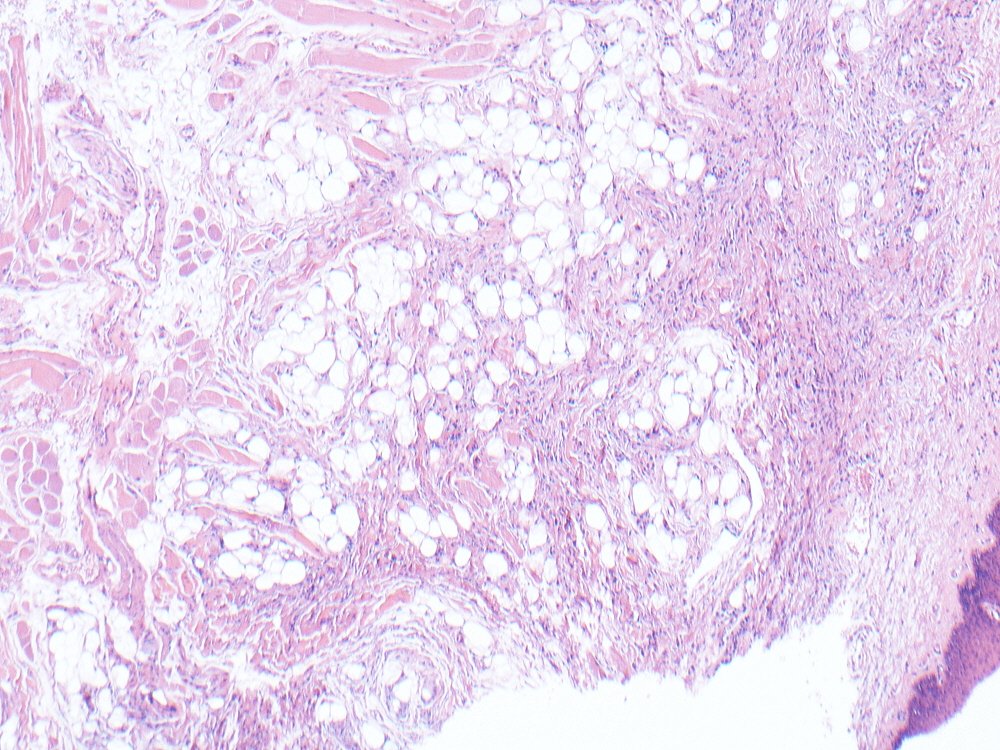

Spindle cell lipoma of the tongue. Spindle cells, ropey collagen, adipocytes, mast cells. Spindle cells CD34+ and show loss of RB expression. #oralpath #pathology #bstpath